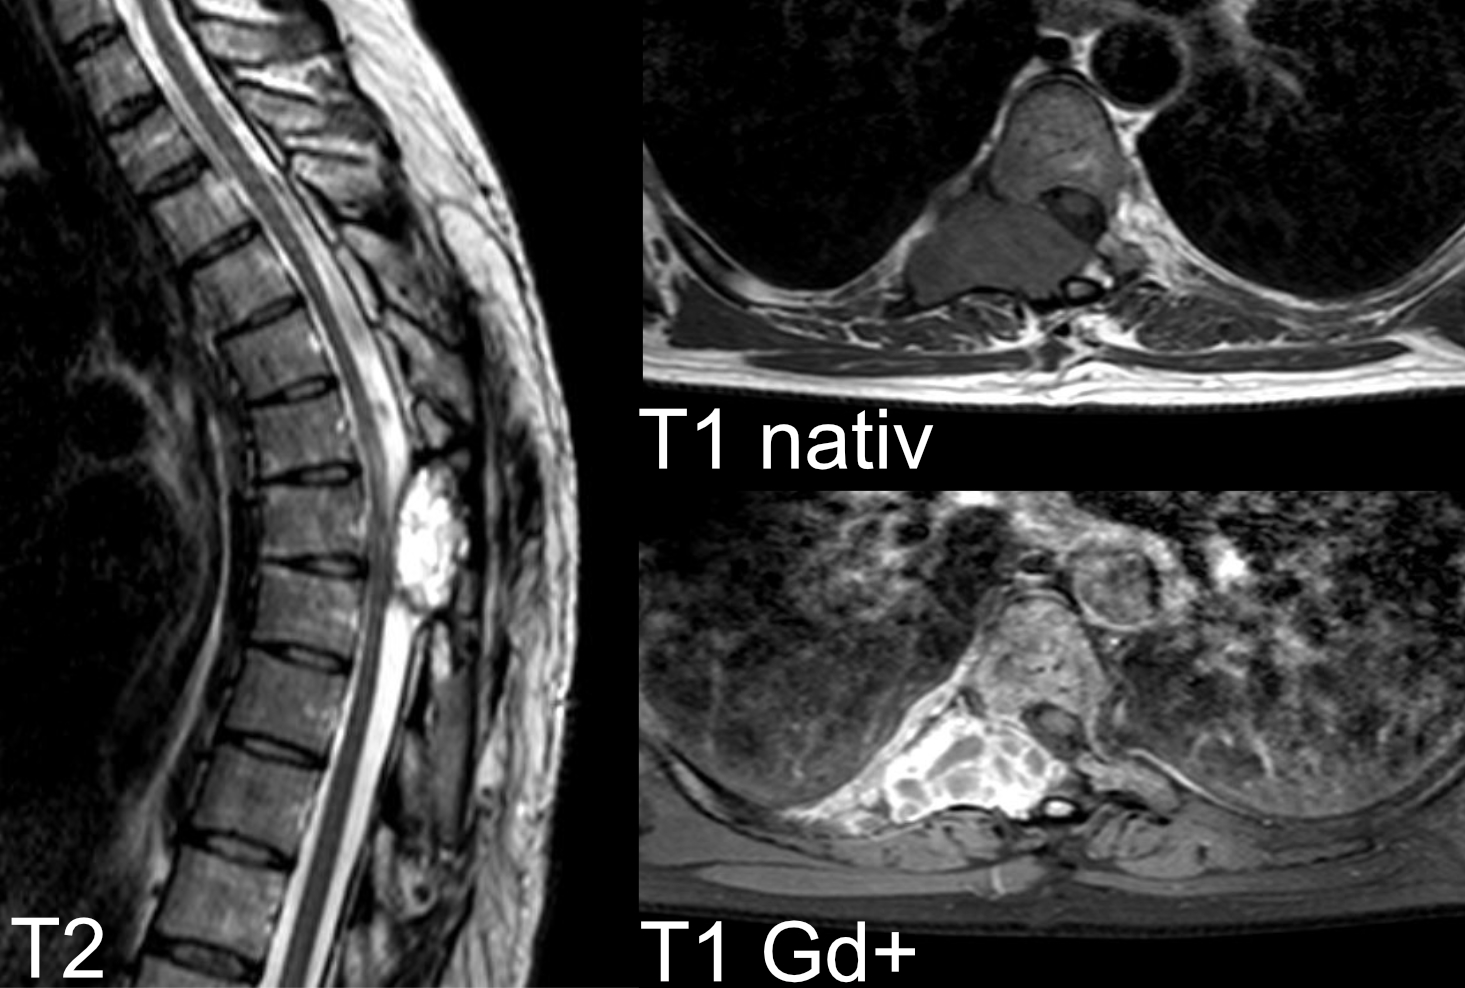

Präoperatives MRT Bild eines histopathologisch verifizierten Riesenzelltumors an der Brustwirbelsäule.

Riesenzelltumor an der Brustwirbelsäule